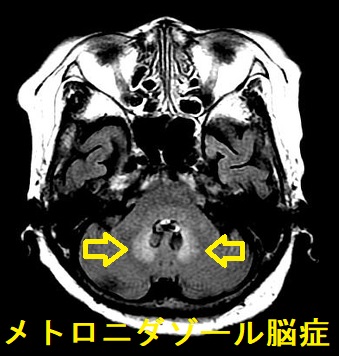

- バンコマイシン散剤内服(静脈用ではない)・メトロニダゾール(フラジール®;アメーバなどの寄生虫,ピロリ菌除菌薬)に切り替える